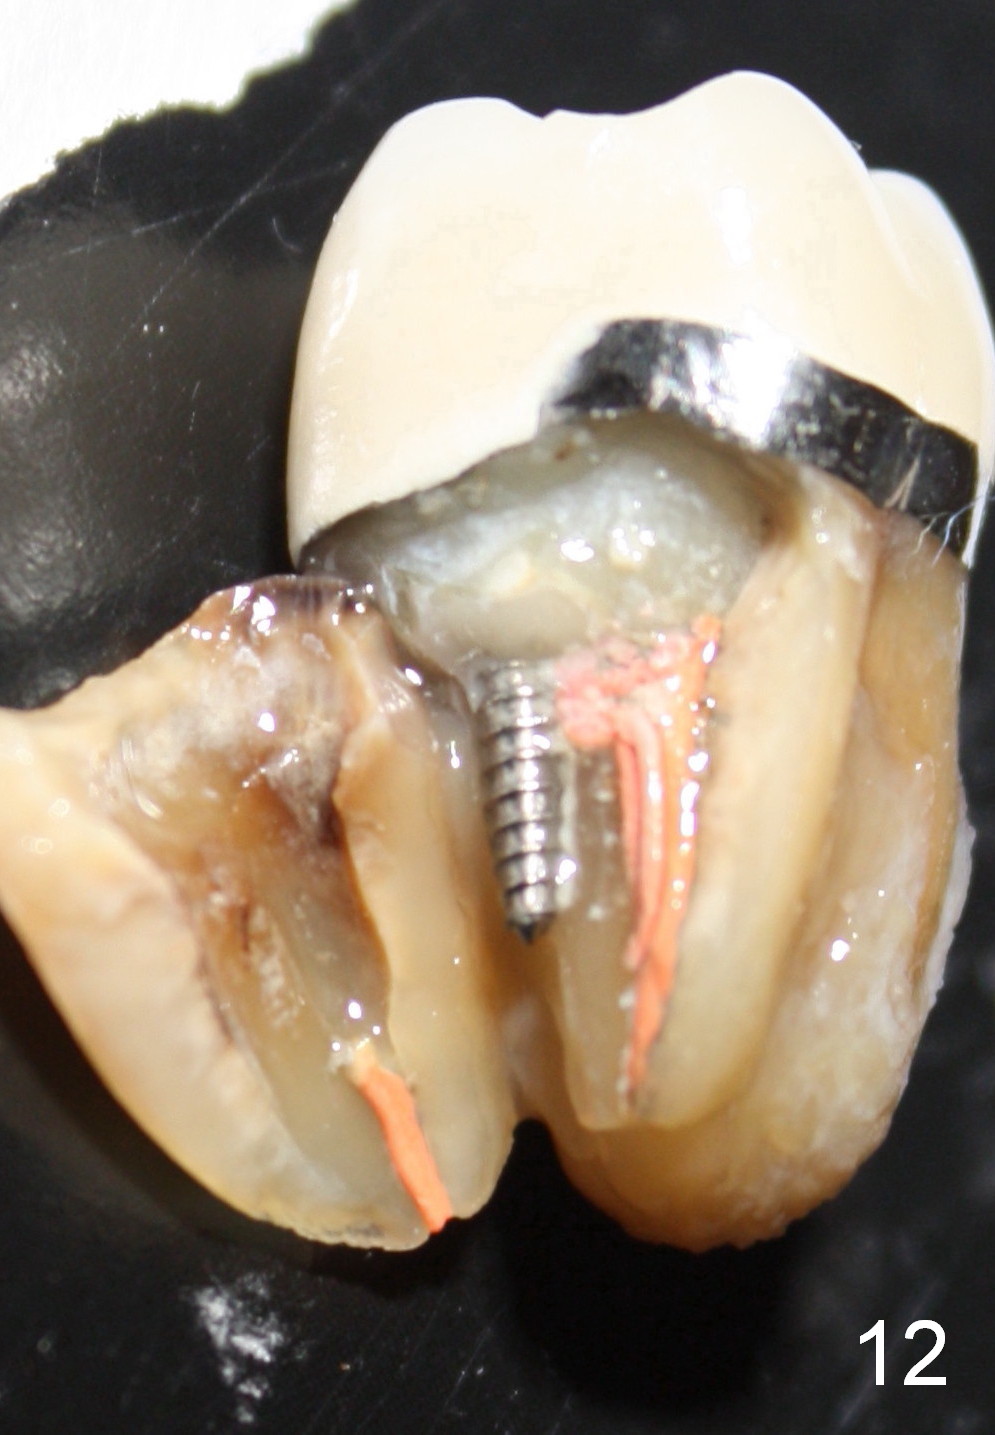

Fig.12 show root fracture associated with mesiobuccal post of the 2nd molar. In contrast the lower right 2nd premolar is intact without crown after root canal therapy. It appears that the post weakens the root.